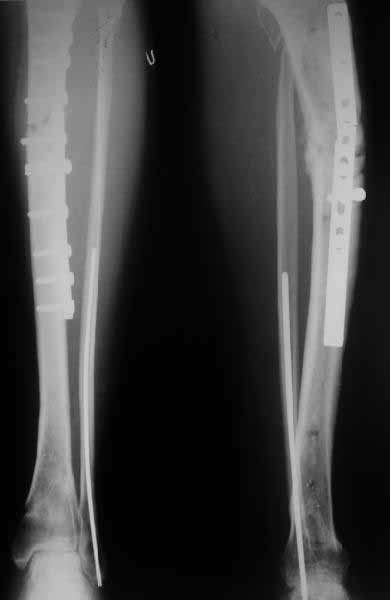

Subject: Unhappy (valgus) tibia nailing

A female 24 years old, a sister of a friend of mine (not physician) living in Moscow, 3 weeks ago admitted to the hospital in Moscow after a car accident (was a pedestrian) with a tibial shaft fracture. 3 days ago closed locked nailing was performed, see attached films. Now he is in panic because they are going to remove the nail and perform plating.

The tibia shaft fracture (proximal 1/3 of the shaft) is apex medial 20 degrees, slightly short and a few degrees apex anterior after nailing. The nail extends quite proximal to the entry site. I wasn't able to see the distal end of the nail on my screen and am not certain if there was distal locking.